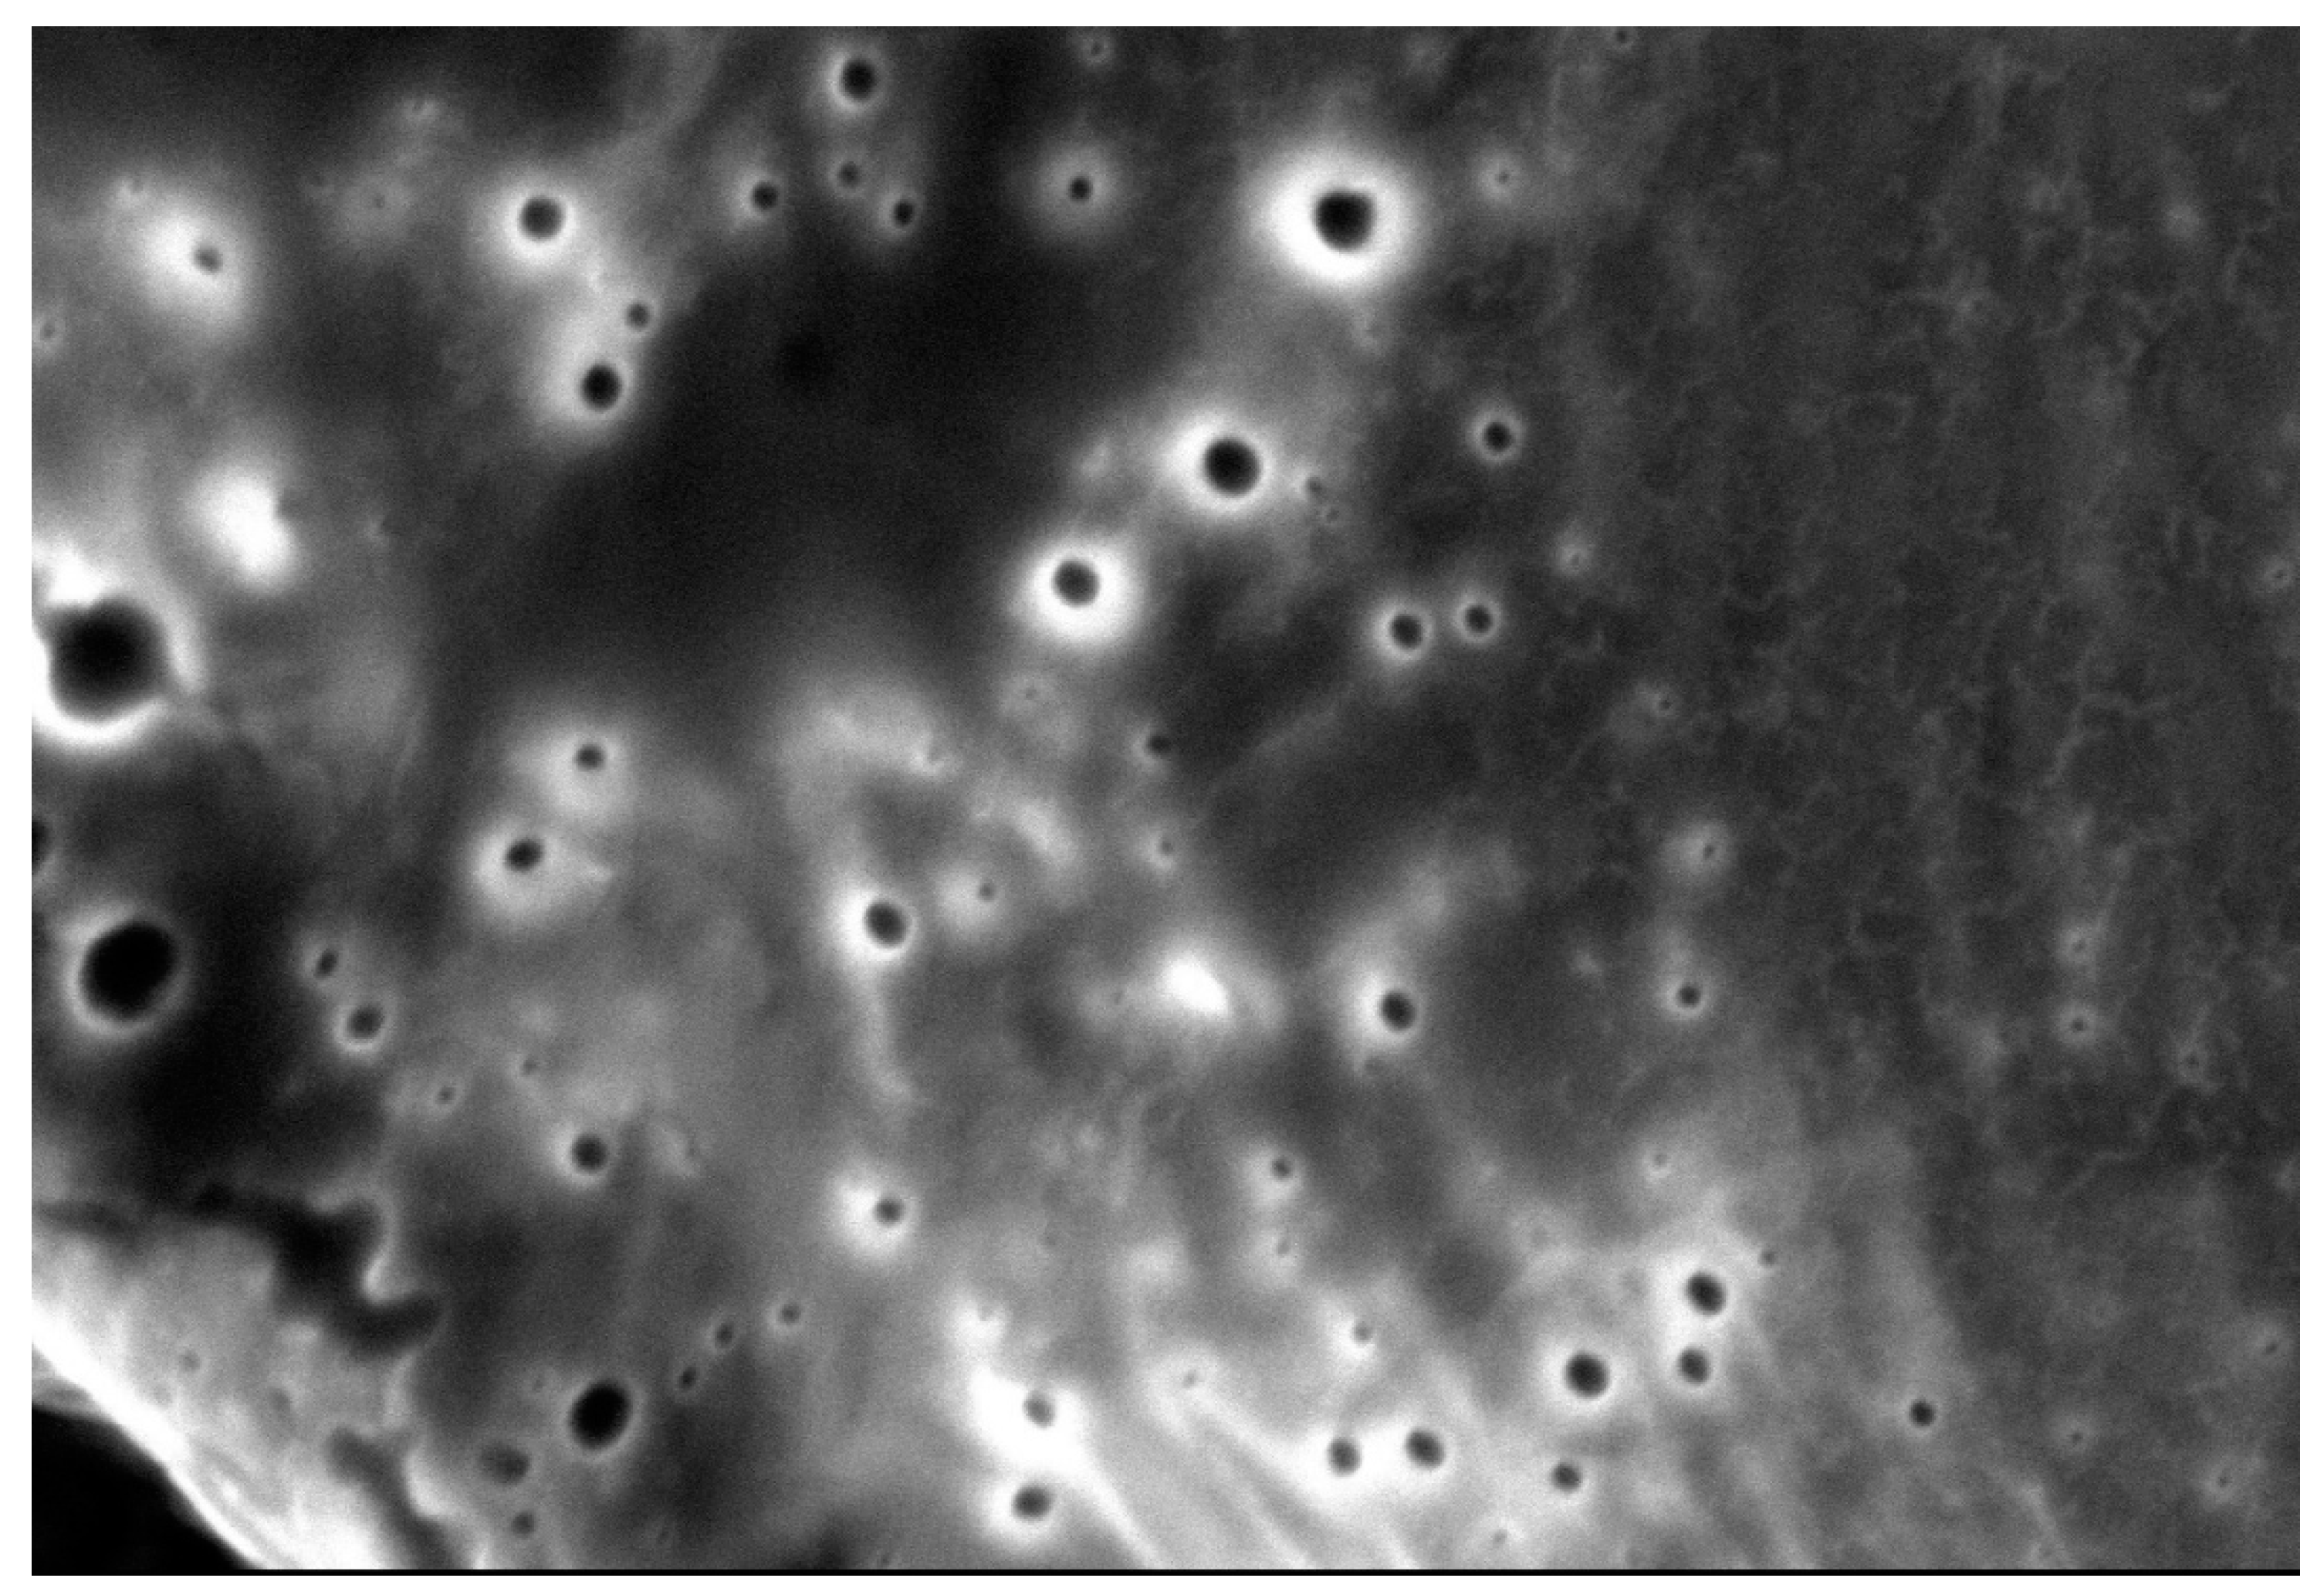

3.1.5. Scanning Electronic Microscopy (SEM)